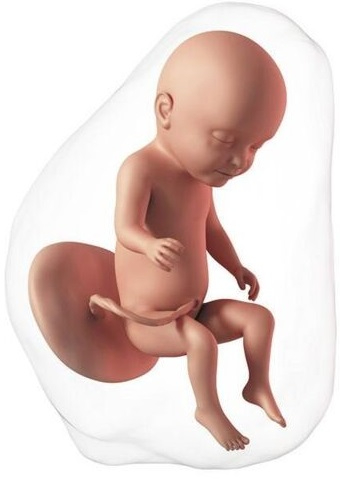

El bebé mide aproximadamente 37-38 cm de la cabeza a los pies y el peso está alrededor de 1300-1350 gramos. En esta semana, inicia el tercer y último trimestre del embarazo. Ahora tiene pestañas, cejas, el cabello empieza a alargarse y puede verse en ecografía. En estos momentos el feto ya empieza a abrir y cerrar los ojos pero aún no puede ver, debido al ambiente oscuro dentro del útero, la visión es el único sentido que no podrá experimentar hasta el nacimiento.

En estos momentos el diámetro de su cabeza todavía es mayor que el de su abdomen, por eso los niños prematuros suelen tener una cabeza más grande en relación al cuerpo. Esta desproporción entre cabeza y abdomen cambia lentamente hasta la semana 35, cuando el diámetro del abdomen pasa a ser mayor que el de la cabeza.

El bebé mide aproximadamente 39 cm de la cabeza a los pies y pesa un kilo y medio. Si previamente tenía la cabeza hacia arriba (estaba sentado o presentación podálica), en esta etapa empieza a ubicarse en la posición adecuada para el parto vaginal, con la cabeza hacia abajo (presentación cefálica). Algunos permanecen en posición podálica hasta el final del embarazo por limitación en la movilidad debido a un cordón umbilical corto o enredado, por la forma del útero o simplemente porque se siente cómodo y feliz así.

Ahora el bebé pesa aproximadamente 1.700 gramos y mide 40 cm de la cabeza a los pies. El aparato respiratorio está casi formado. Los alvéolos (pequeñas bolsas a donde ingresa el aire) están muy desarrollados, por lo cual ya cuenta con un área suficiente para el intercambio de oxígeno y dióxido de carbono entre los pulmones y la sangre que llevará a cabo al momento del nacimiento.

Debido a la acumulación de grasa bajo la piel, ésta tiene un aspecto rosado y su cara se puede observar más redondeada. El vérnix caseoso, la sustancia blanquecina con función protectora de la piel sigue aumentando.

El peso del bebé es de aproximadamente 1.900 gramos y mide en promedio 42 cm de la cabeza a los pies.

Su apariencia es muy similar a la que tendrá a la hora del nacimiento, pero más pequeño. El pelo y las uñas crecen rápidamente, por esto al nacer se deben cortar para evitar que se "rayen" la cara.